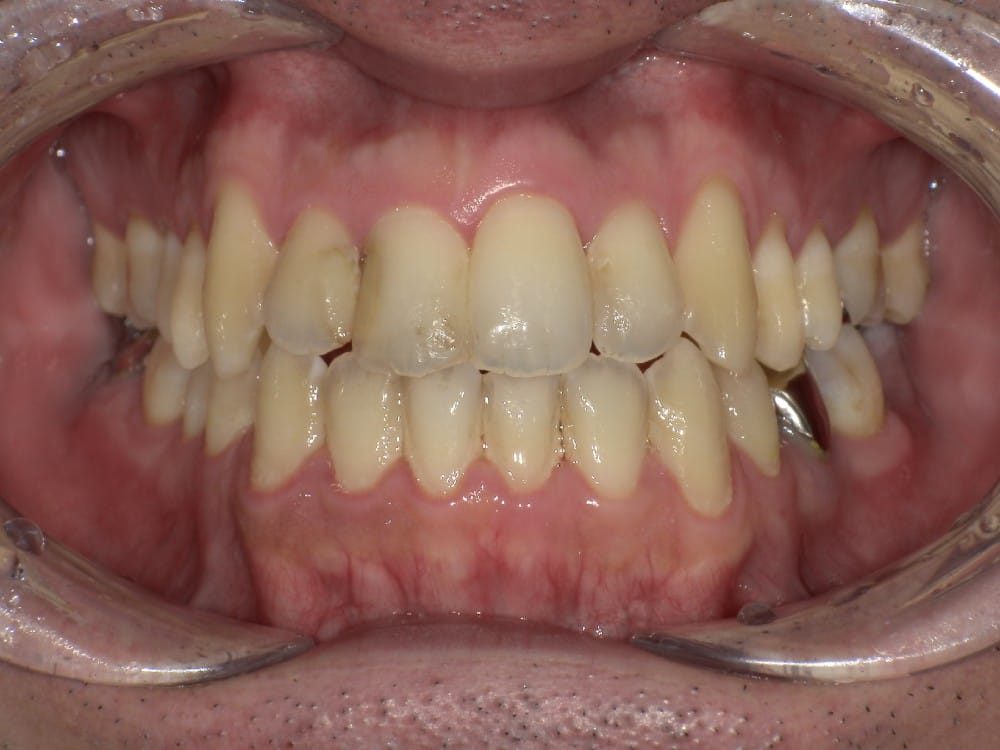

(case2)

もう1ケース治療途中のケースでありますが、受け口を治すことで若干の横顔の改善が見られたケースを紹介します。

30代の女性で、受け口とガタガタを主訴にご来院されました。

治療前

分析しますと

- 骨格的な上下あごの前後差は中等度〜重度

- 噛み合わせの位置も下あごの奥歯が半分くらい前にズレていた

- 上の前歯が内側に傾斜している

というケースで、外科的な処置も検討するようなケースでした。

骨格的なズレや奥歯の噛み合わせのズレもあり、重度の受け口でしたが、上あごの前歯が内側に傾斜しているため、本来の歯の軸に戻すことで、受け口を改善できると診断し、治療を開始しました。

先ほどのケースと同じように、患者さまに外科的な手術の選択肢も提示しましたが、希望されず、横顔の変化はおそらく起こらないことを納得の上、治療をスタートいたしました。

今回のケースも奥歯の移動量が大きいため、マウスピースだけでは難しいと判断し、カリエールとよばれる装置を補助的に使用し、上下の噛み合わせの前後関係を整えることで、手術を行わずに機能面と見た目の両方が改善することにしました。

治療中の直近の写真です。生まれつき小さな歯である前から両側の2番目の歯は、被せ物をして見た目の回復をする予定にしています。

<治療前と現在の比較です>

矯正治療によって前歯の被さりを改善することで、先ほどの症例ほどではありませんが、下唇の突出感が減り、上唇も正常な位置に戻り、横顔がやわらかい印象に変化しました。